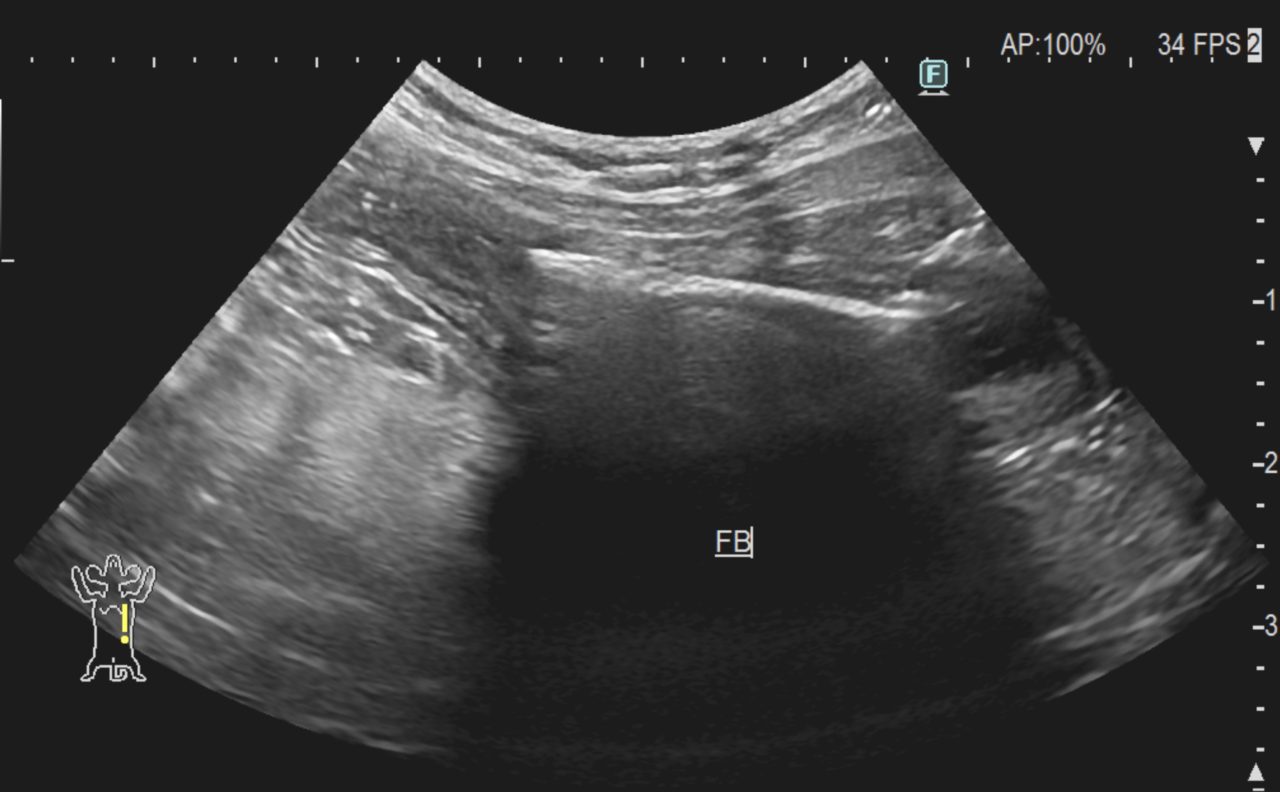

猫と生活している方はジョイントマット(スポンジ状)に気をつけてください。猫は噛み心地が良いのか噛みちぎって食べてしまうようです。別々のご家庭で生活している2頭の猫さんが腸閉塞を起こしたとの事で緊急で腸切開を行いました。偶然にも2頭ともジョイントマットの切れ端が閉塞を起こしていました。この事故は繰り返すかもしれないので念のためジョイントマットは撤去するか、猫のいないところで使用した方が良さそうです。